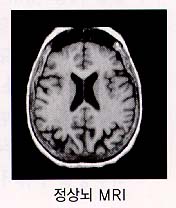

Ä¡¸Å¿¡ ¼÷·ÃµÈ Àǻ簡 ÁøÂû°ú ¿©·¯ °Ë»ç °úÁ¤À» ÅëÇÏ¿© Ä¡·á°¡ °¡´ÉÇÑ Áúȯ¿¡ ÀÇÇÑ Ä¡¸ÅÀÎÁö, ¾ËÂêÇÏÀ̸Ӽº Ä¡¸ÅÀÎÁö¸¦ È®ÀÎÇÏ°Ô µË´Ï´Ù. °Ë»ç¿¡´Â Ç÷¾×°Ë»ç, ´¢°Ë»ç, ÈäºÎ¹æ»ç¼±°Ë»ç, ½ÉÀüµµ³úÆÄ°Ë»ç ¹× Àڱ⠰ø¸í°Ë»ç(MRI) µîÀÌ ÀÖ½À´Ï´Ù. ÃÖ±Ù¿¡´Â ÀÌ °Ë»ç ¿Ü¿¡µµ À¯ÀüÀÚ °Ë»ç¿Í ¾çÀüÀÚ ¹æÃâ ´ÜÃþ ÃÔ¿µ¼ú(PET)À» ÀÌ¿ëÇÏ¿© ÃʱâÀÇ ¾ËÂêÇÏÀ̸Ӻ´ ȯÀÚµéÀ» º¸´Ù Á¤È®ÇÏ°Ô Áø´ÜÇÒ ¼ö ÀÖÀ¸³ª, ¾ÆÁ÷±îÁö È®ÁøÀº ȯÀÚ°¡ µ¹¾Æ°¡½Å ÈÄ »çÈĺΰËÀ» ÅëÇÑ ³úÁ¶Á÷ °Ë»ç¿¡ ÀÇÇØ¼¸¸ ÇÒ ¼ö ÀÖ½À´Ï´Ù.

Áø´Ü ¾ËÂêÇÏÀ̸Ӻ´°ú ¸¶Âù°¡Áö·Î Ä¡¸Å¿¡ ¼÷·ÃµÈ Àǻ簡 ÁøÂû°ú ¿©·¯ °Ë»ç °úÁ¤À» ÅëÇÏ¿© Ç÷°ü¼ºÄ¡¸ÅÀÎÁö ¾Æ´Ï¸é ´Ù¸¥ ¿øÀο¡ ÀÇÇÑ Ä¡¸ÅÀÎÁö¸¦ È®ÀÎÇϰԵ˴ϴÙ.

°Ë»ç¿¡´Â Ç÷¾×°Ë»ç, ´¢°Ë»ç, ÈäºÎ¹æ»ç¼±°Ë»ç, ½ÉÀüµµ ³úÆÄ°Ë»ç ¹× ÀÚ±â°ø¸í°Ë»ç(MRI) µîÀÌ ÀÖ½À´Ï´Ù. Ä¡¸Å Áõ»óÀÌ ÀÖÀ¸¸é¼ ½Å°æÇÐÀû °Ë»ç»ó ÀÌ»ó¼Ò°ßÀÌ ÀÖ°í ³ú ÃÔ¿µ»ó ±× ÀÌ»ó¼Ò°ßÀ» µÞ¹ÞħÇÒ ¼ö ÀÖ´Â ¼Ò°ßÀÌ º¸À̸é È®ÁøÇÒ ¼ö ÀÖ½À´Ï´Ù.